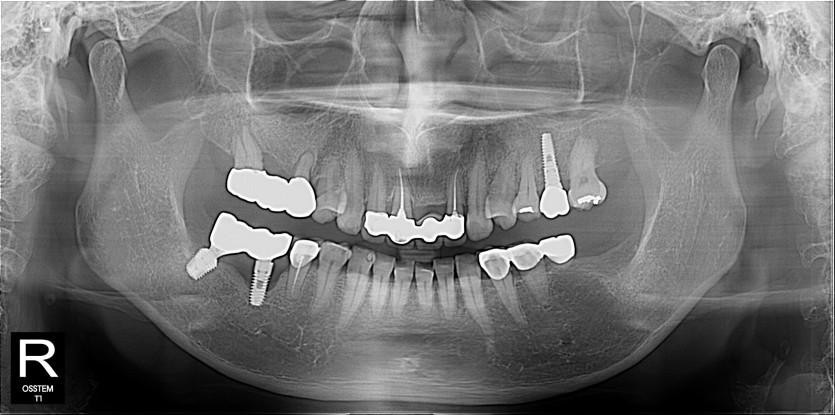

임플란트 사례